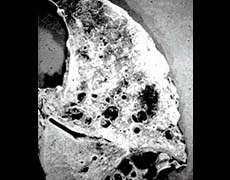

a damaged lung

a damaged lung

What happened to it?

clogged with thick mucus

clogged with thick mucus

Why?

a disease called cystic fibrosis

a disease called cystic fibrosis

Effects:

made breathing difficult

made breathing difficult

caused lung infections

caused lung infections